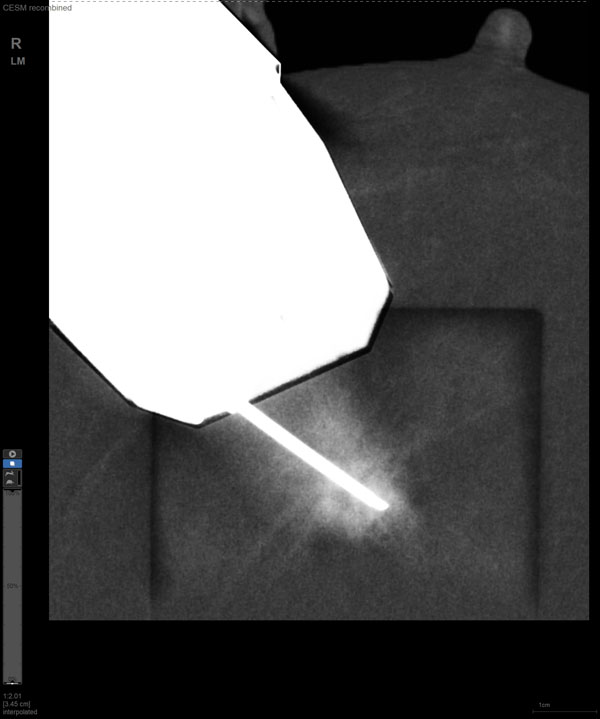

某患者增强磁共振成像MRI显示肿瘤周边有活性,中心区域有组织坏死。为得到准确的病理结果,穿刺靶区需避开肿物坏死区域。在与患者主管医生充分讨论后,放射科医生为患者行CEM引导下穿刺活检术。术中,CEM检查肿物同样显示为环形强化,巧妙避开坏死区域后,穿刺靶区选择了肿物增强早期明显强化区域,术程顺利,仅用时15分钟。术后该患者病理结果为浸润性导管癌Ⅱ级。

国内首台具有数字乳腺断层摄影(DBT)和CEM引导下穿刺功能的X线机